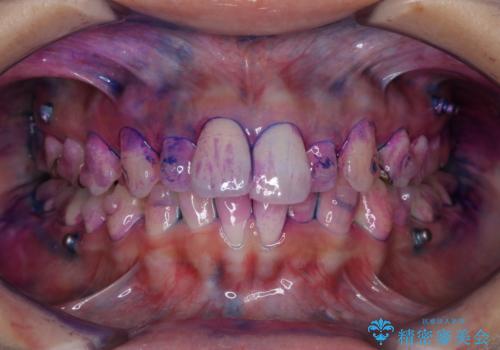

磨けているようでも、染出しをして目に見えるプラーク(歯垢)を確認することで、より正しいブラッシング方法を身につけることができます。インビザライン中は、歯にアタッチメントをつけるため、歯の表面がデコボコしてプラークが付きやすい状態になります。毎日のケアでしっかりと汚れを落として虫歯や歯周病・口臭のリスクを減らしていくことが大切です。定期的にメンテナンスを行い、ケアがどれくらい出来ているか確認したり歯科医院で専門的な機械や器具によるPMTCを行うことをおススメします。